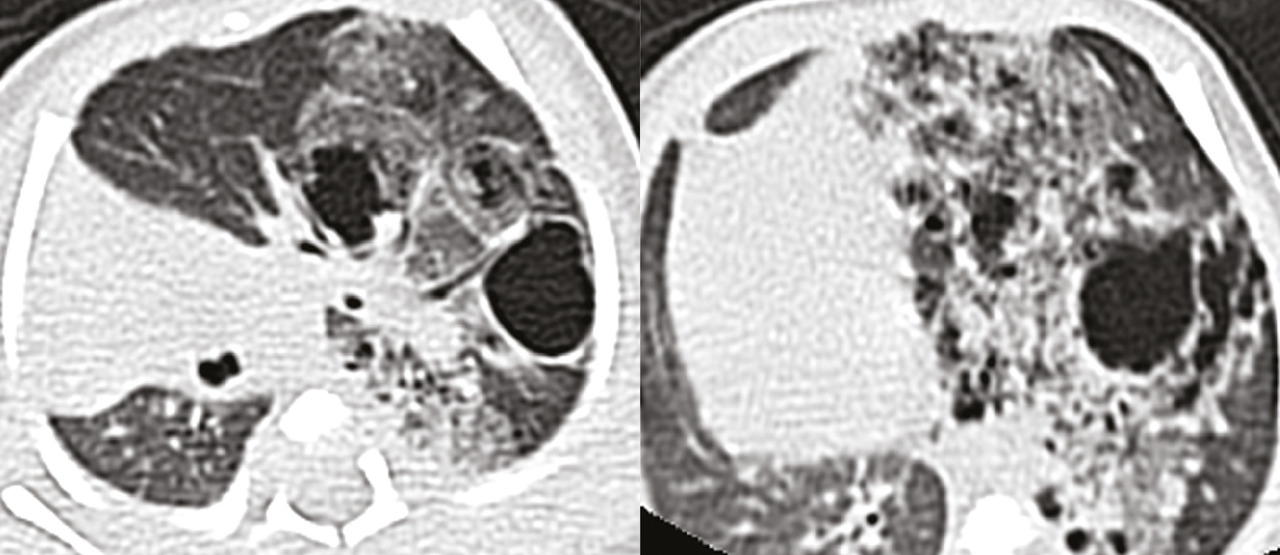

Le scanner thoracique ou tomodensitométrie (TDM) montre de multiples lésions kystiques au sein d’une condensation parenchymateuse pulmonaire prenant la quasi-totalité du poumon gauche, typiques d’une malformation adénomatoïde kystique classée type I de la classification d’Adzick (fig. 2).

Le diagnostic post-natal est fondé sur le scanner thoracique, qui est l’examen de référence.1 La sémiologie radiologique est variable : une condensation homogène (souvent avant aération des kystes en post-natal immédiat), des images kystiques multiples, l’association d’images kystiques et d’une condensation, un niveau hydroaérique avec épaississement de la paroi des kystes en cas de surinfection. La prédominance lobaire inférieure, unilatérale, est retrouvée dans 98 % des cas.